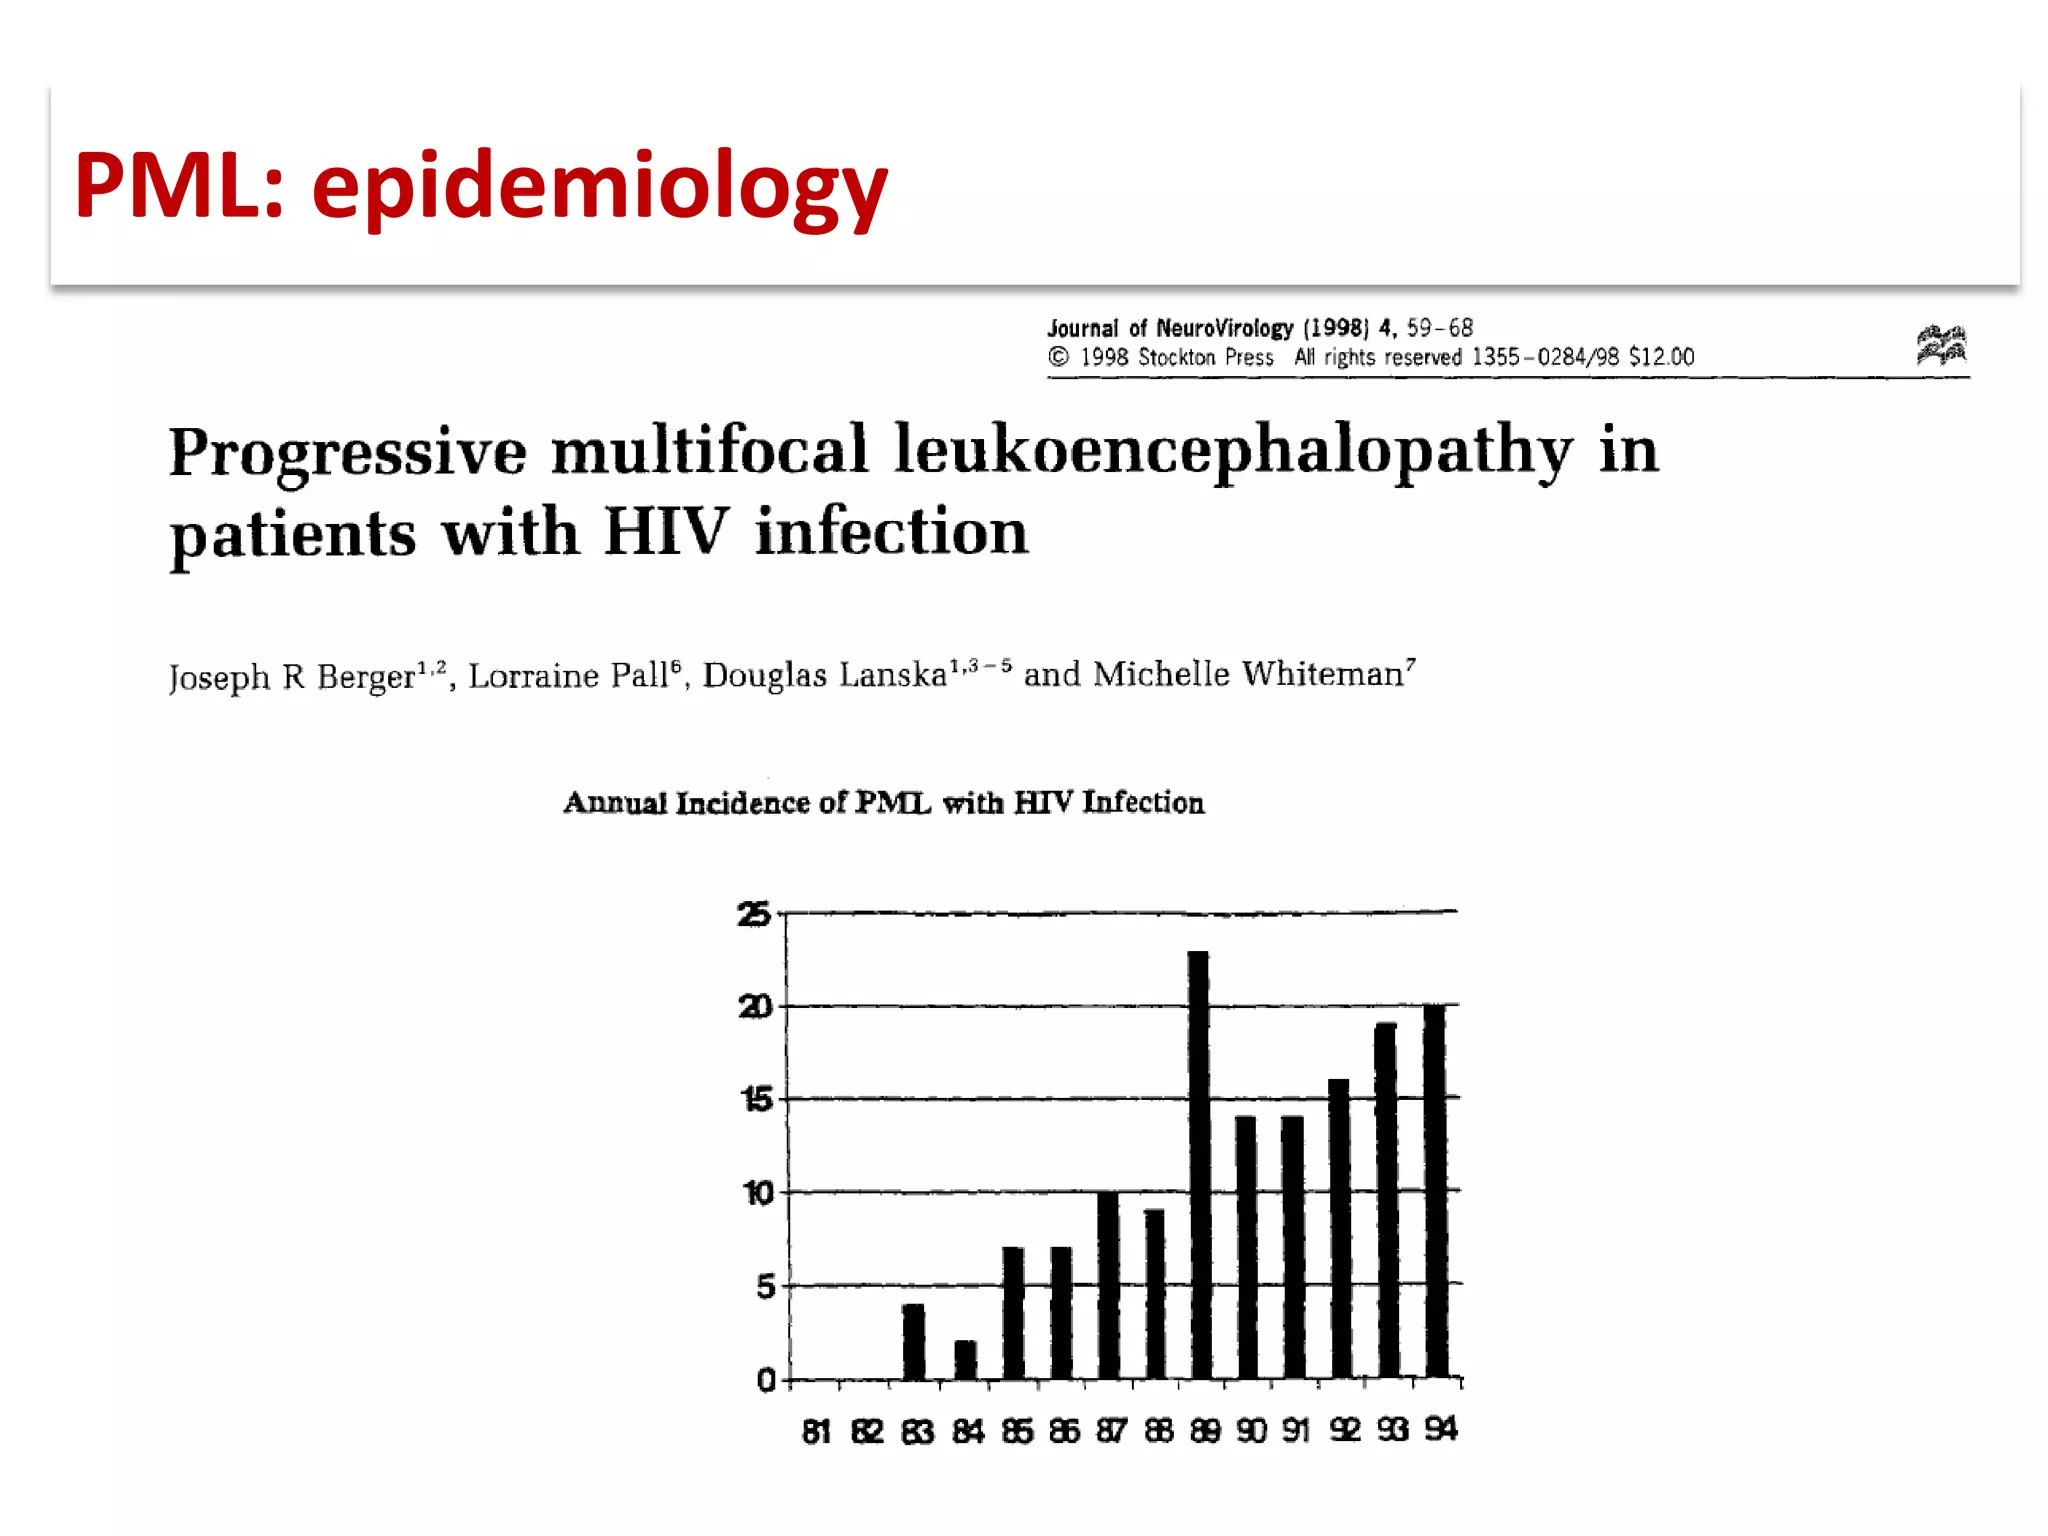

This document discusses progressive multifocal leukoencephalopathy (PML), an opportunistic infection caused by the John Cunningham virus (JCV) that leads to demyelination in the central nervous system. It highlights the epidemiology, clinical manifestations, diagnostic methods, and risk factors associated with PML, particularly in immunocompromised patients and those undergoing immunomodulatory therapies. It also presents data on the incidence of PML in patients treated with natalizumab and other therapies, addressing the relationships between these treatments and the development of PML.